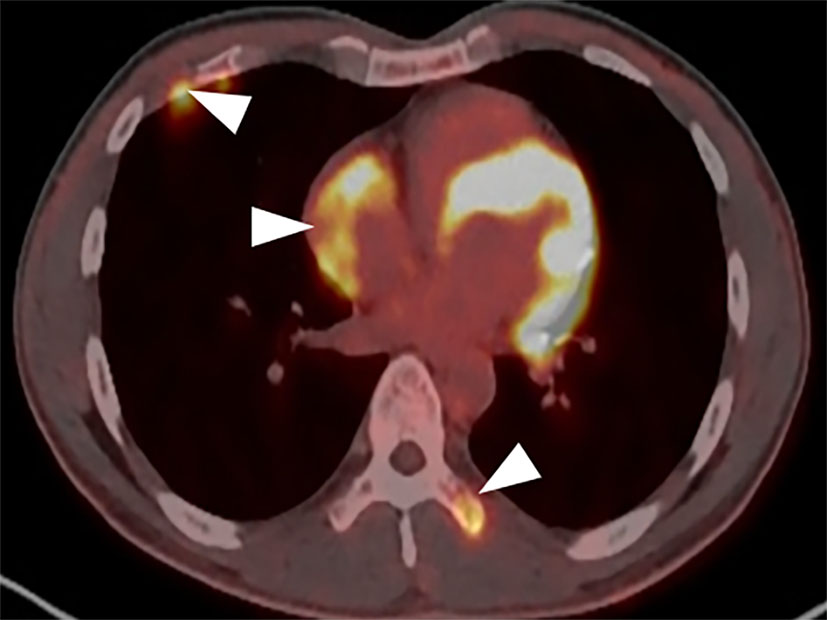

A CT examination from the chest to the pelvis was performed, which revealed a right atrial mass, multiple small ground-glass pulmonary nodules, and bone destructions (Figures 1A–D). Transthoracic echocardiography (TTE) showed an ill-defined hypoechoic mass of approximately 3.8 cm × 2.3 cm, attached to the lateral wall of the right atrium. Cardiac MRI (CMRI) exhibited a right atrial tumor and multiple pulmonary lesions. On steady-state free precession (SSFP) cine imaging planned in the four chambers, the tumor showed isointense (Figure 2A). On T2-short tau inversion recovery (STIR) sequence images, the tumor displayed high-signal intensity (Figure 2B). On enhanced MRI, the tumor showed arterial heterogeneous enhancement and progressive but incomplete enhancement in the delayed phase (dynamic acquisition) (Figures 2C,D). The patient was referred for 18F-fluorodeoxyglucose (FDG) positron emission tomography-CT (PET-CT) for further characterization of the cardiac mass and systemic evaluation. PET-CT images demonstrated that the right atrial tumor had intensely increased FDG uptake (standardized uptake value, SUVmax, 8.4) with signs of pulmonary and bony metastases (Figure 3). These preoperative images characterized the mass as highly suspicious for a malignant cardiac tumor with multiple metastases.

Figure 3

PET-CT demonstrates the tumor intensely increased FDG uptake with bony metastases (arrowhead).

Positron emission tomography/CT has advantages in non-invasively characterizing cardiac tumors and disease staging, scarce case reports have described the use of FDG PET-CT in differentiating the benign and malignant mass, metastatic workup, preoperative staging, and assessment of response to treatment in primary cardiac angiosarcomas (16–19). Rahbar et al. (20) in their study of various cardiac tumors proposed that malignancy was determined with a sensitivity of 100% and specificity of 86% (accuracy, 96%) after a cutoff with high sensitivity (SUVmax of 3.5) was chosen to avoid false-negatives. In our case, the SUV max of the tumor is 8.4, which is highly suspicious of malignancy.